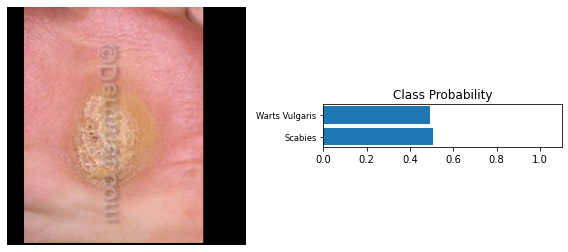

Refer to caption

Figure 12: Results for Warts Vulgaris

The results show us that skin disease diagnosis is very possible with image analysis. We were able to detect the diseases from the images with very high accuracies: 63%, 88% and 57% which are all reasonable scores. When these scores are backed with historical data, we can more confidently diagnose patients. However, we do not provide much information on the historical processing. This will follow in a future research paper. We also restricted the number of classes/diseases to five only so that we could operate within the limits of colab training time.